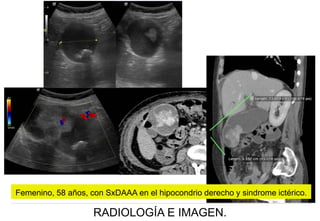

Femenino, 58 años, con SxDAAA en el hipocondrio derecho y sindrome ictérico.

Masa intravesicular AdenoCa de VB; LE,

Femenino, 58 años, con SxDAAA en el hipocondrio derecho y síndrome ictérico.